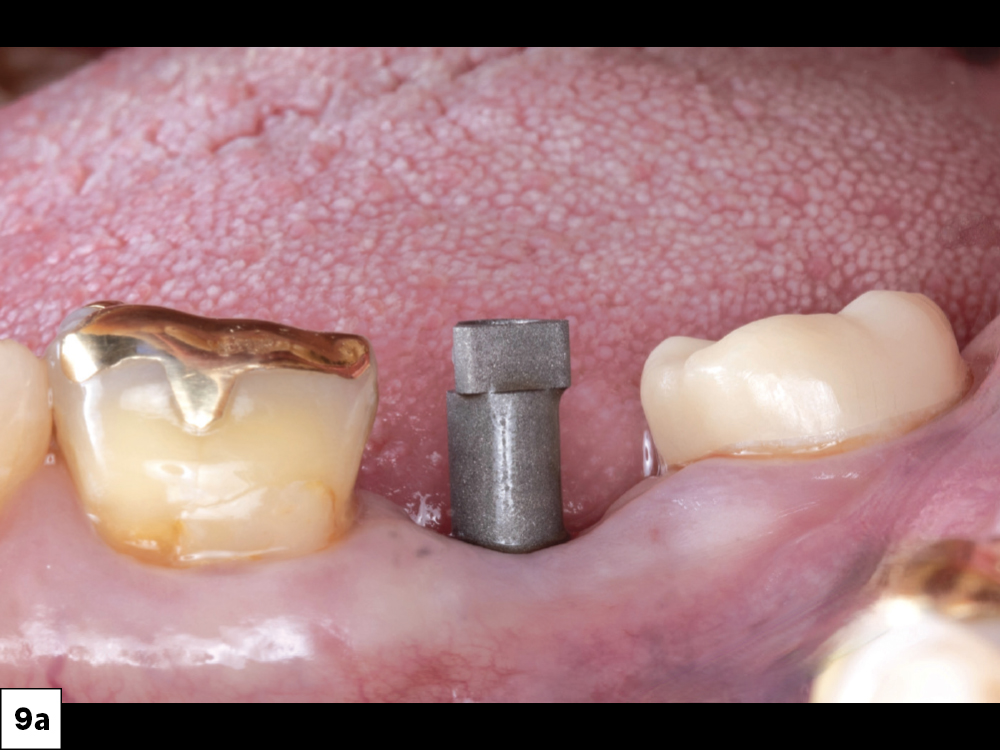

Inclusive Titanium Scan Body

Inclusive® Titanium Scan Body in radiograph

Figures 9a, 9b: An Inclusive® Titanium Scan Body (Glidewell Direct) was placed, and proper seating was confirmed with a radiograph.